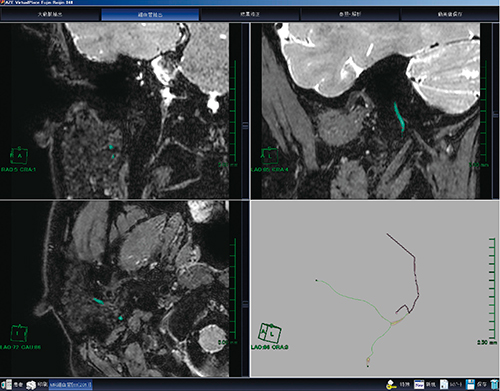

実際の解析方法を図3に示す。最初に大動脈の場所を設定しなければならないが,顔面神経では,そのような構造が存在しないので,頭蓋外の顔面神経の起始部を大動脈と見立てて設定する。次に,冠動脈の抽出と同様に顔面神経の起始部から末梢に向かって細かくマウスをクリックし,神経を抽出していく。冠動脈では,ある程度抽出すればオートで抽出できるが,顔面神経では構造の細かさ,信号の弱さからうまくいかない。そのため,マニュアルですべてクリックしていくことが必要となる。1本の神経の抽出が終わったら,分枝を同様に抽出していく。すべての抽出が完了すると,全体像描出のためにpartial width(PW)MIP表示を行う。このようにして作成した耳下腺内顔面神経が図4である。顔面神経が耳下腺を貫く様子が描出されている。

図3 “MR細血管解析”を用いた解析方法

3断面を詳細に観察しながら神経の抽出を行う。